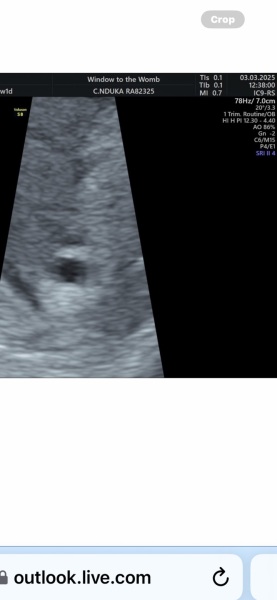

booJo24902 · 03/03/2025 16:42

Lmp-19/01/25

Today I should be 6 weeks + 1

(I think I'm more 5)

Had my first very faint positive on 17th feb went to epu on 24th where they scanned me and saw nothing because my levels were only 63 and Sunday my levels were 167. So epu called and said they will see me on 12th March.

I went for an early scan today and the guy who scanned me said they can't see a sac just haemorrhage in my womb. I thought they saw a sac but he said ' I wouldn't call it a sac at this stage'

I will post what he said and the scan pic.